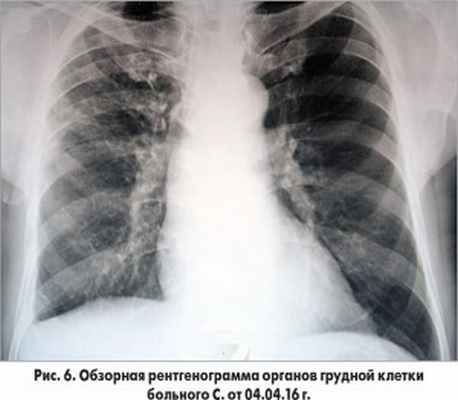

Пациент продолжал получать ацетилсалициловую кислоту, клопидогрель, аторвастатин, эналаприл, бисопролол, пантопразол, эплеренон. На рентгенограмме от 4.04.2016 г. (70-е сутки наблюдения) отмечалась выраженная положительная динамика в виде рассасывания инфильтративных изменений в легких и исчезновения плеврального выпота (рис. 6).